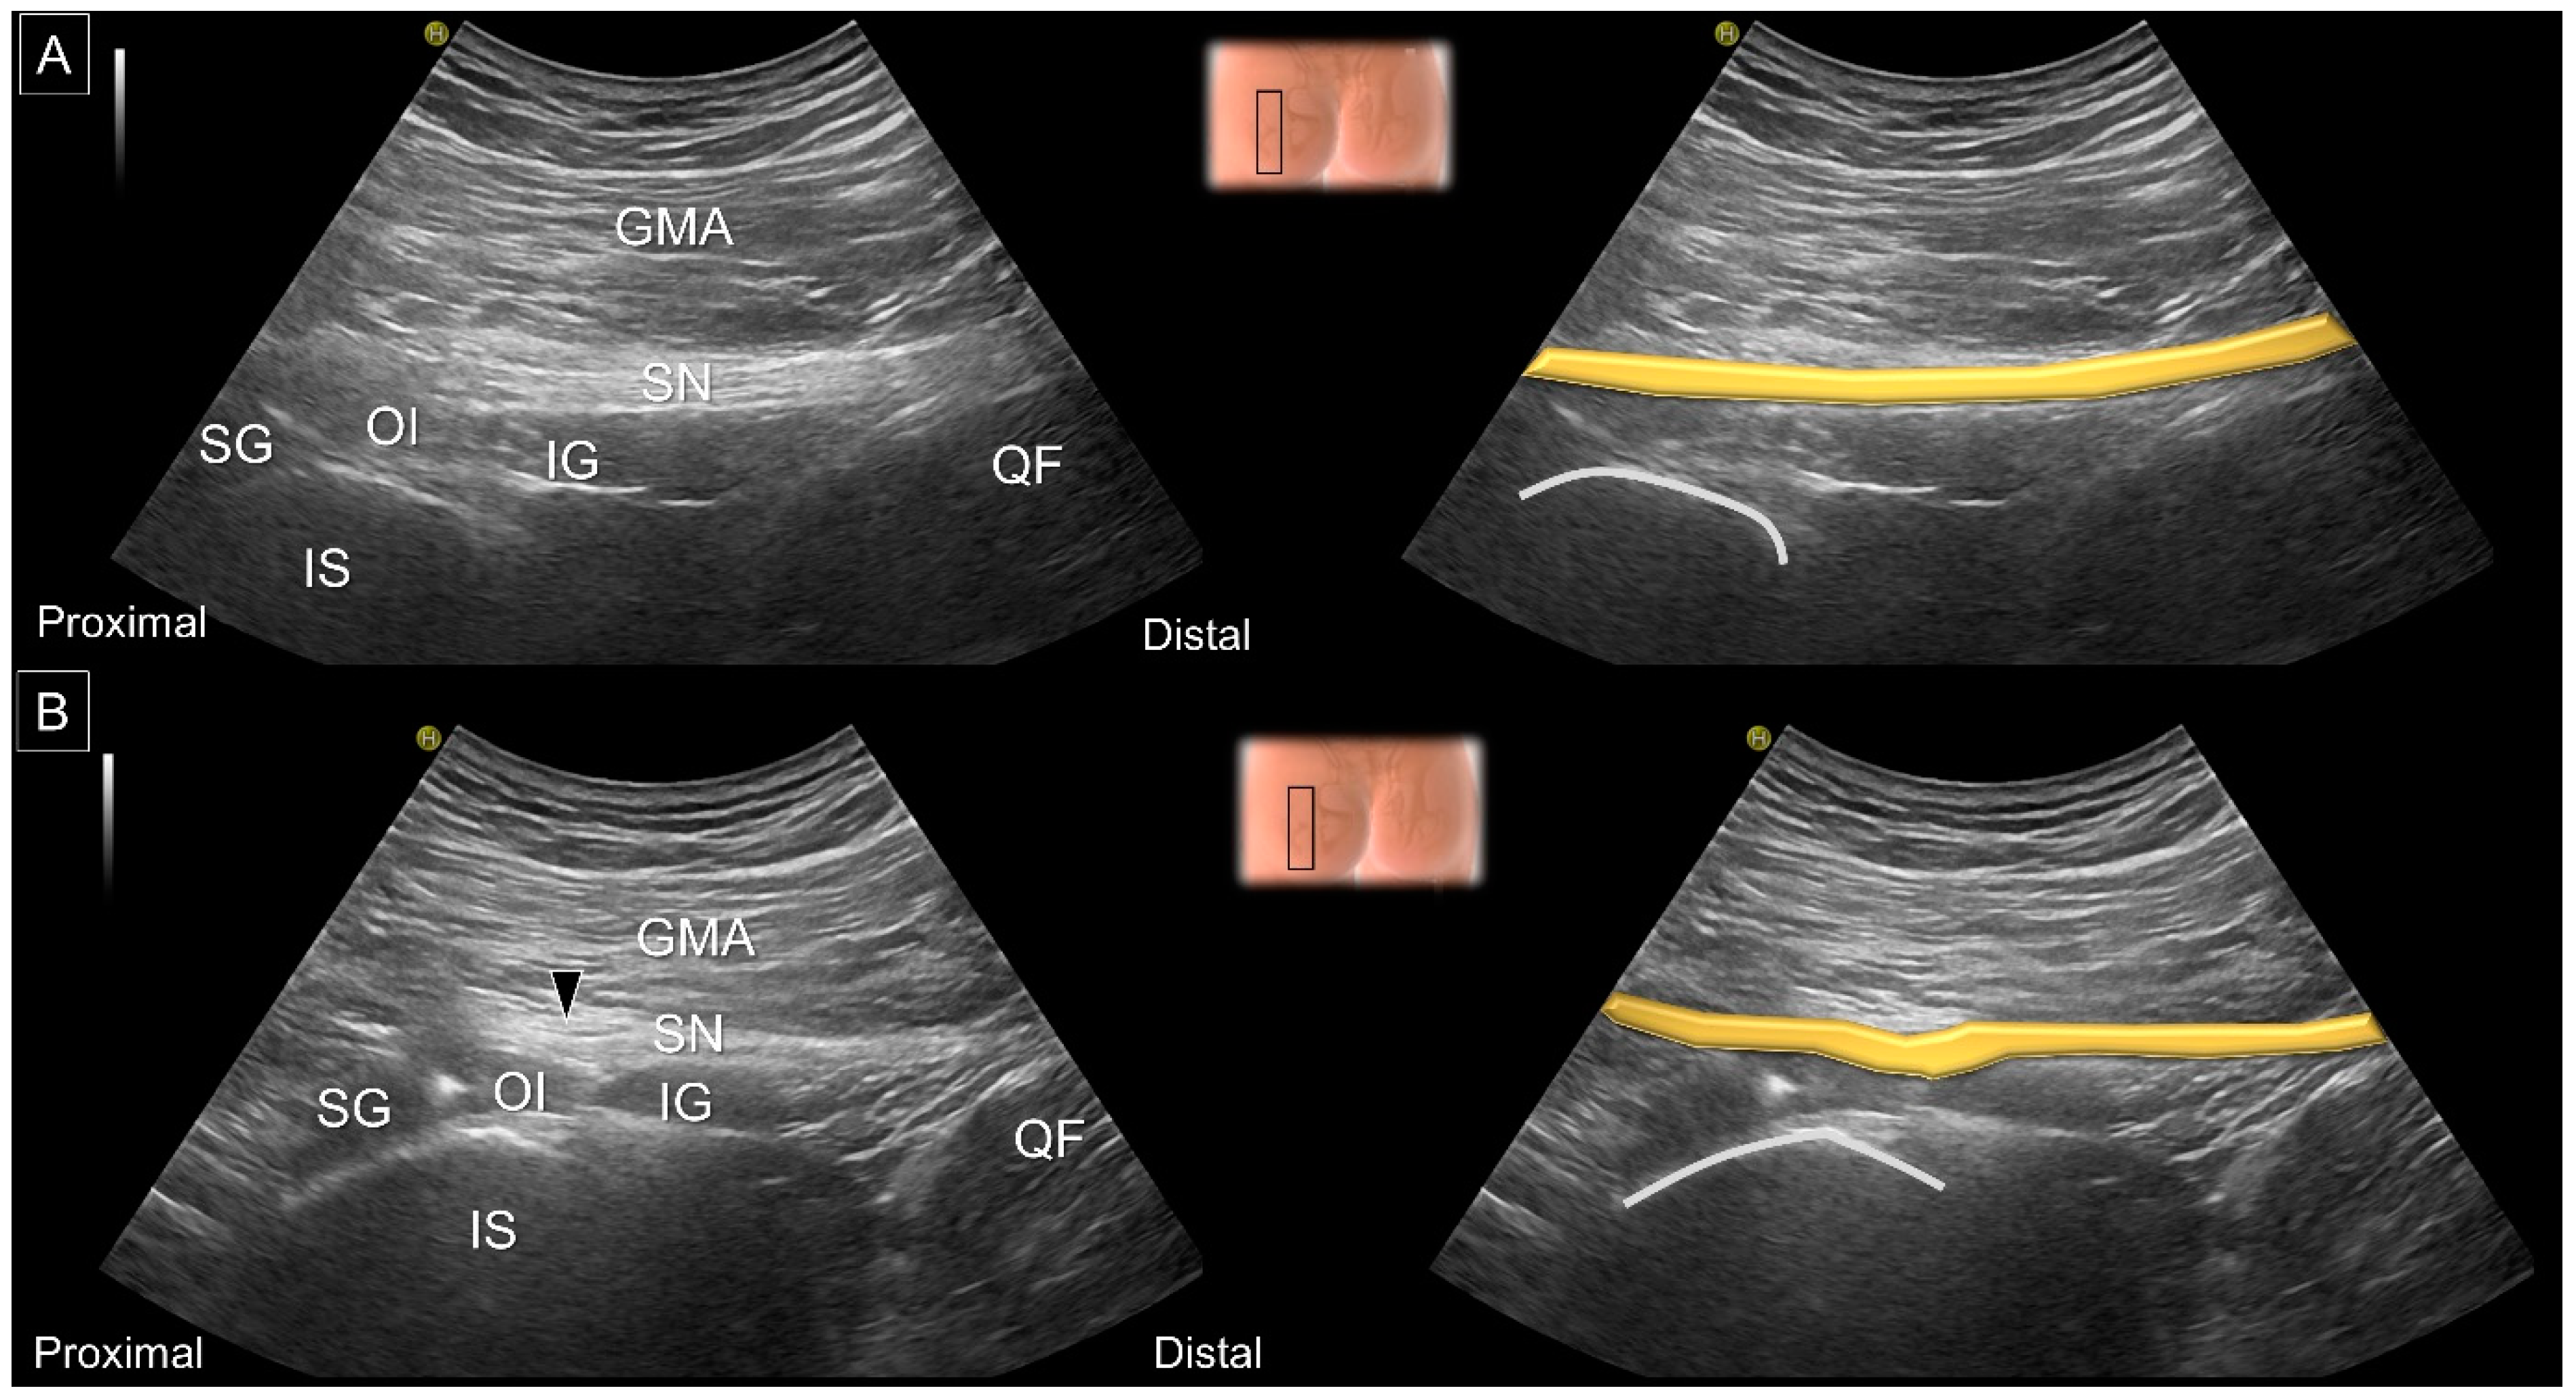

8. Dynamic Ultrasound Evaluation